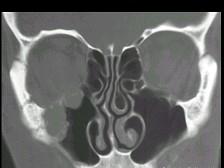

女性,50岁,右鼻塞、脓涕3个月,CT、MRI检查如图所示,请选择正确的答案 ( )

• A.右侧上颌窦积液

• B.右侧上颌窦腺样囊性癌

• C.右侧上颌窦粘膜下囊肿

• D.右侧上颌窦黏液腺瘤

• E.右侧上颌窦黏液囊肿

答案: B